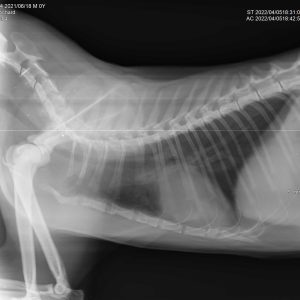

El diagnóstico por imagen es una herramienta fundamental en la medicina veterinaria moderna, ya que permite evaluar de forma precisa y no invasiva las estructuras internas del paciente. A través de técnicas avanzadas como la radiografía digital y la ecografía, es posible identificar alteraciones anatómicas y funcionales que facilitan un diagnóstico temprano y un manejo clínico más eficaz.

Nuestro servicio en Mastervet está orientado a ofrecer estudios de alta calidad, con equipos actualizados y protocolos adaptados a cada caso. Realizamos evaluaciones completas que incluyen la interpretación detallada de las imágenes y la emisión de informes clínicos claros, contribuyendo a la toma de decisiones terapéuticas.

Trabajamos en estrecha colaboración con veterinarios clínicos para asegurar una correcta correlación entre los hallazgos de imagen y la situación clínica del paciente, optimizando así el abordaje diagnóstico y el seguimiento evolutivo.